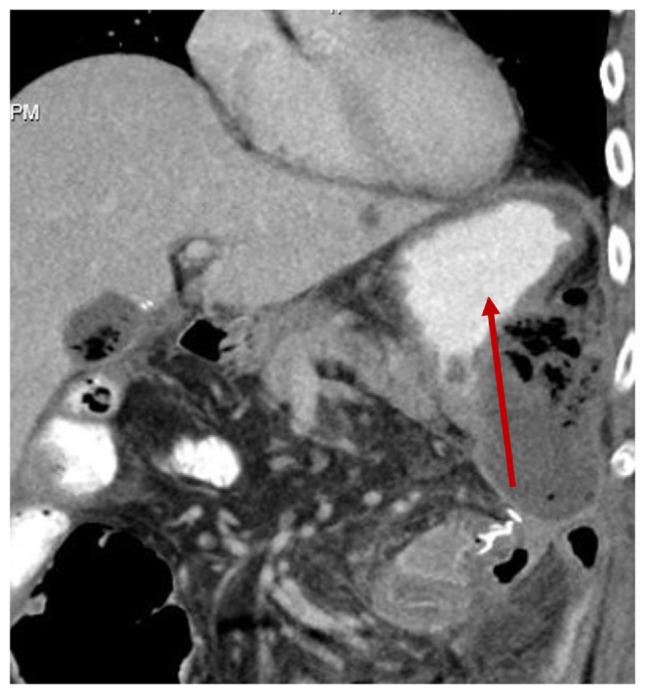

Coccidioides is a fungus endemic to the Southwestern United States, known for causing Valley Fever. While typically asymptomatic or presenting as a respiratory tract infection, rare cases of disseminated infection to the peritoneum have been reported. The patient in this case study presented with a small bowel obstruction, requiring an exploratory laparoscopy showing evidence of an inflammatory mass with a jejuna-colic fistula with adherence to the spleen. The patient underwent splenectomy with a cholecystectomy and small bowel resection. Intraabdominal cultures revealed Coccidioides, and so he started long-term antifungal treatment. The patient was also initiated on salvage chemotherapy for DLBCL, and ultimately received CAR T-Cell therapy at a tertiary center. This case report highlights a unique presentation of gastrointestinal Coccidioides infection, in the setting of an immunocompromised host with a hematologic malignancy. It also provides insight into the therapeutic challenges clinicians face when treating complicated patients such as this who require urgent chemotherapy while risking further immunosuppression in the setting of active infection.

球孢子菌是一种美国西南部特有的真菌,以引起山谷热而闻名。虽然通常无症状或表现为呼吸道感染,但也有罕见的播散至腹膜感染的病例报道。本病例研究中的患者表现为小肠梗阻,需要进行 exploratory laparoscopy(此处可能有误,推测为“ exploratory laparotomy”即剖腹探查术),结果显示有炎性肿块、空肠结肠瘘并与脾脏粘连。患者接受了脾切除术、胆囊切除术和小肠切除术。腹腔内培养发现了球孢子菌,因此他开始接受长期抗真菌治疗。该患者还开始接受弥漫性大 B 细胞淋巴瘤(DLBCL)的挽救性化疗,最终在一家三级中心接受了嵌合抗原受体 T 细胞(CAR T-Cell)治疗。本病例报告强调了在免疫功能低下且患有血液系统恶性肿瘤的宿主中,胃肠道球孢子菌感染的独特表现。它还揭示了临床医生在治疗此类复杂患者时所面临的治疗挑战,这些患者需要紧急化疗,同时在有活动性感染的情况下又有进一步免疫抑制的风险。